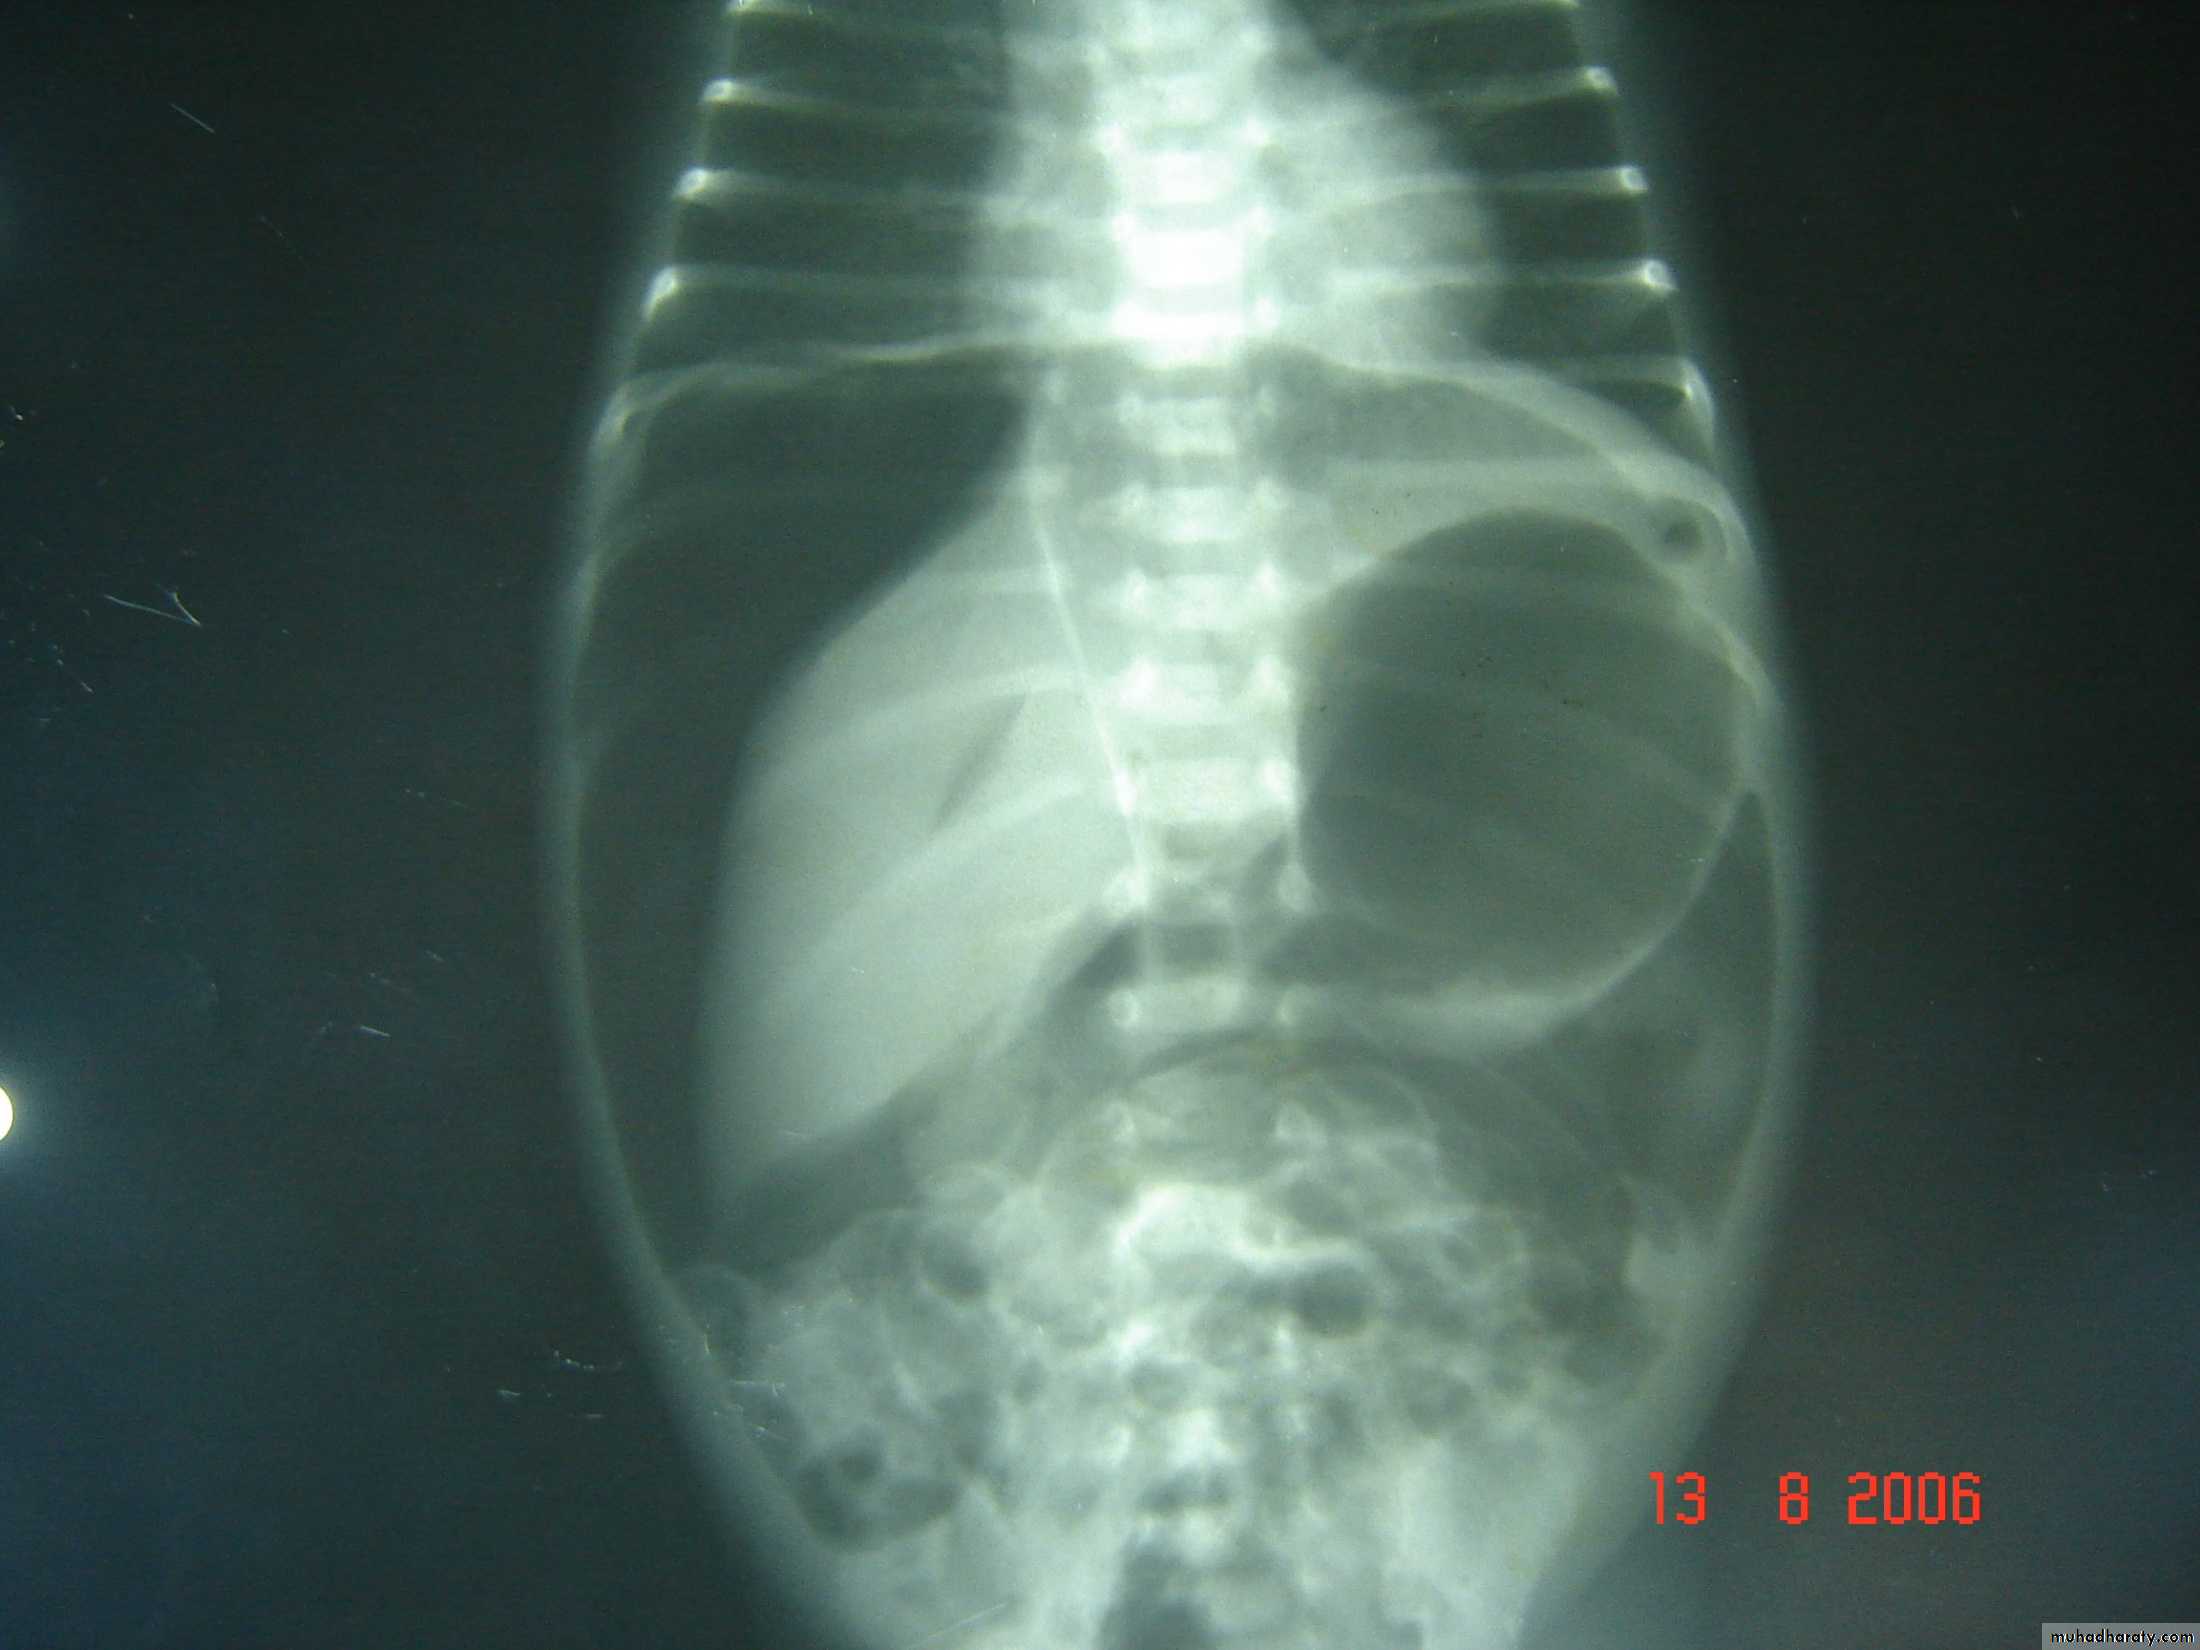

N.E.C

Tutorial